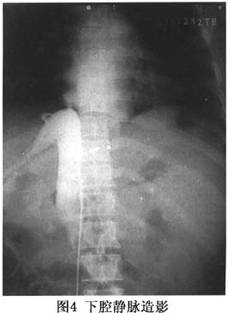

5.8.4 血管造影

血管造影是明確BCS病變部位的最重要方法。一般可通過以下3種方法瞭解肝靜脈及下腔靜脈形態和血流動力學變化(圖3,4,5)。

(1)經股靜脈下腔靜脈插管:下腔靜脈完全性梗阻時,導管不能進入正常距離,向上逐漸出現阻抗,測壓見下腔靜脈壓顯著升高;如果有下腔靜脈阻塞時,需同時經頸靜脈上腔靜脈插管作雙向造影,可清晰顯示膜性結構的形態和阻塞距離的長短。此時,在阻塞部位以下可見附壁血栓,更可清晰顯示迂曲、擴張的腰靜脈、腰升靜脈、脊柱前靜脈、膈靜脈及心包膈靜脈,亦可見血流經奇靜脈。可見一支或二支肝靜脈阻塞,阻塞下段擴張,或一支阻塞、另一支代償性擴張,亦可見各支肝靜脈間的分流。若沒有下腔靜脈阻塞,操作嫺熟者導管不能進入靜脈,提示肝靜脈有梗阻。

6.8.2.1 (1)下腔靜脈造影

採用Seldinger技術,行股靜脈穿刺,經導絲將導管引至下腔靜脈肝段,首先測定下腔靜脈壓(IVCP),此時造影可明確阻塞的程度和部位、局部病變的形態及側支循環形成情況。必要時,可同時經頸靜脈或貴要靜脈插管,經上腔靜脈、右心房再至下腔靜脈上段,作對端造影,更可清晰顯示阻塞部位、程度、範圍和側支循環狀況。對病變的形態,隔膜的厚度,中央是否有孔或呈篩狀,可呈現噴壺嘴徵或沙漏徵,隔膜附着方式是水平天幕狀或斜形僧帽狀,有無膜下血栓繁衍,有無附壁血栓等均可有所瞭解。若肝靜脈開口部位於隔膜之下且並無受阻時,在下腔靜脈顯影的同時,肝靜脈亦可顯影(圖4)。此時,還可見心包膈靜脈、腰靜脈、膈靜脈、腰升靜脈及椎前靜脈的擴張顯影。總之,下腔靜脈造影,即便是單向造影,一般情況下,結合臨牀,可以對B-CS做出診斷,對少數病例,可行對端插管做雙向造影。